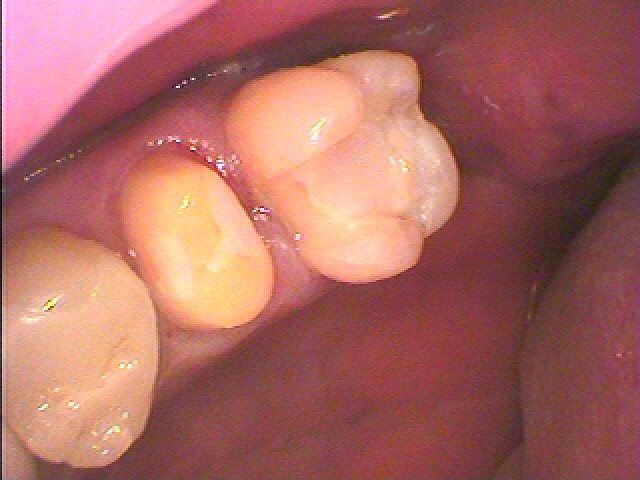

穂p県のクラウンが入っていました 物が詰まる 噛むと痛むが主訴でした セラミックを用いた審美治療|お知らせ |広島市安佐南区の歯科医院 穂p県のクラウンが入っていました 物が詰まる 噛むと痛むが主訴でした セラミックを用いた審美治療 トップ お知らせ・ブログ お知らせ 穂p県のクラウンが入っていました 物が詰まる 噛むと痛むが主訴でした セラミックを用いた審美治療 穂p県のクラウンが入っていました 物が詰まる 噛むと痛むが主訴でした セラミックを用いた審美治療 歯の間に隙間が空いていました 根管治療からやり直しています ファイバーコアを建てていきました セレックセラミックにて被せを作成しています このように本来の歯のように被せが入りました 左上の被せになります 生活歯でした セレックセラミッククラウンにて修復しています Web診療予約 初めての方へ 選ばれ続ける理由 院内設備について 歯が痛いしみる一般歯科 歯がぐらぐらする歯周病 健康な歯を保ちたい予防歯科 子供の虫歯予防をしたい小児歯科 銀歯をセラミックに審美歯科 白い歯を目指しませんか?ホワイトニング 矯正専門医がいるので安心矯正歯科 抜けた歯を補いたいインプラント・入れ歯 医院案内 スタッフ紹介 メリィハウス歯科クリニックオフィシャルホームページ ラベンダー歯科クリニックオフィシャルホームページ お知らせ・ブログ ホーム 診療科目 一般歯科 歯周病治療 予防治療 小児歯科 審美治療 ホワイトニング 矯正歯科 入れ歯・インプラント マウスピース矯正 初めての方へ 院長・スタッフ 設備紹介 医院案内・アクセス メニューを閉じる